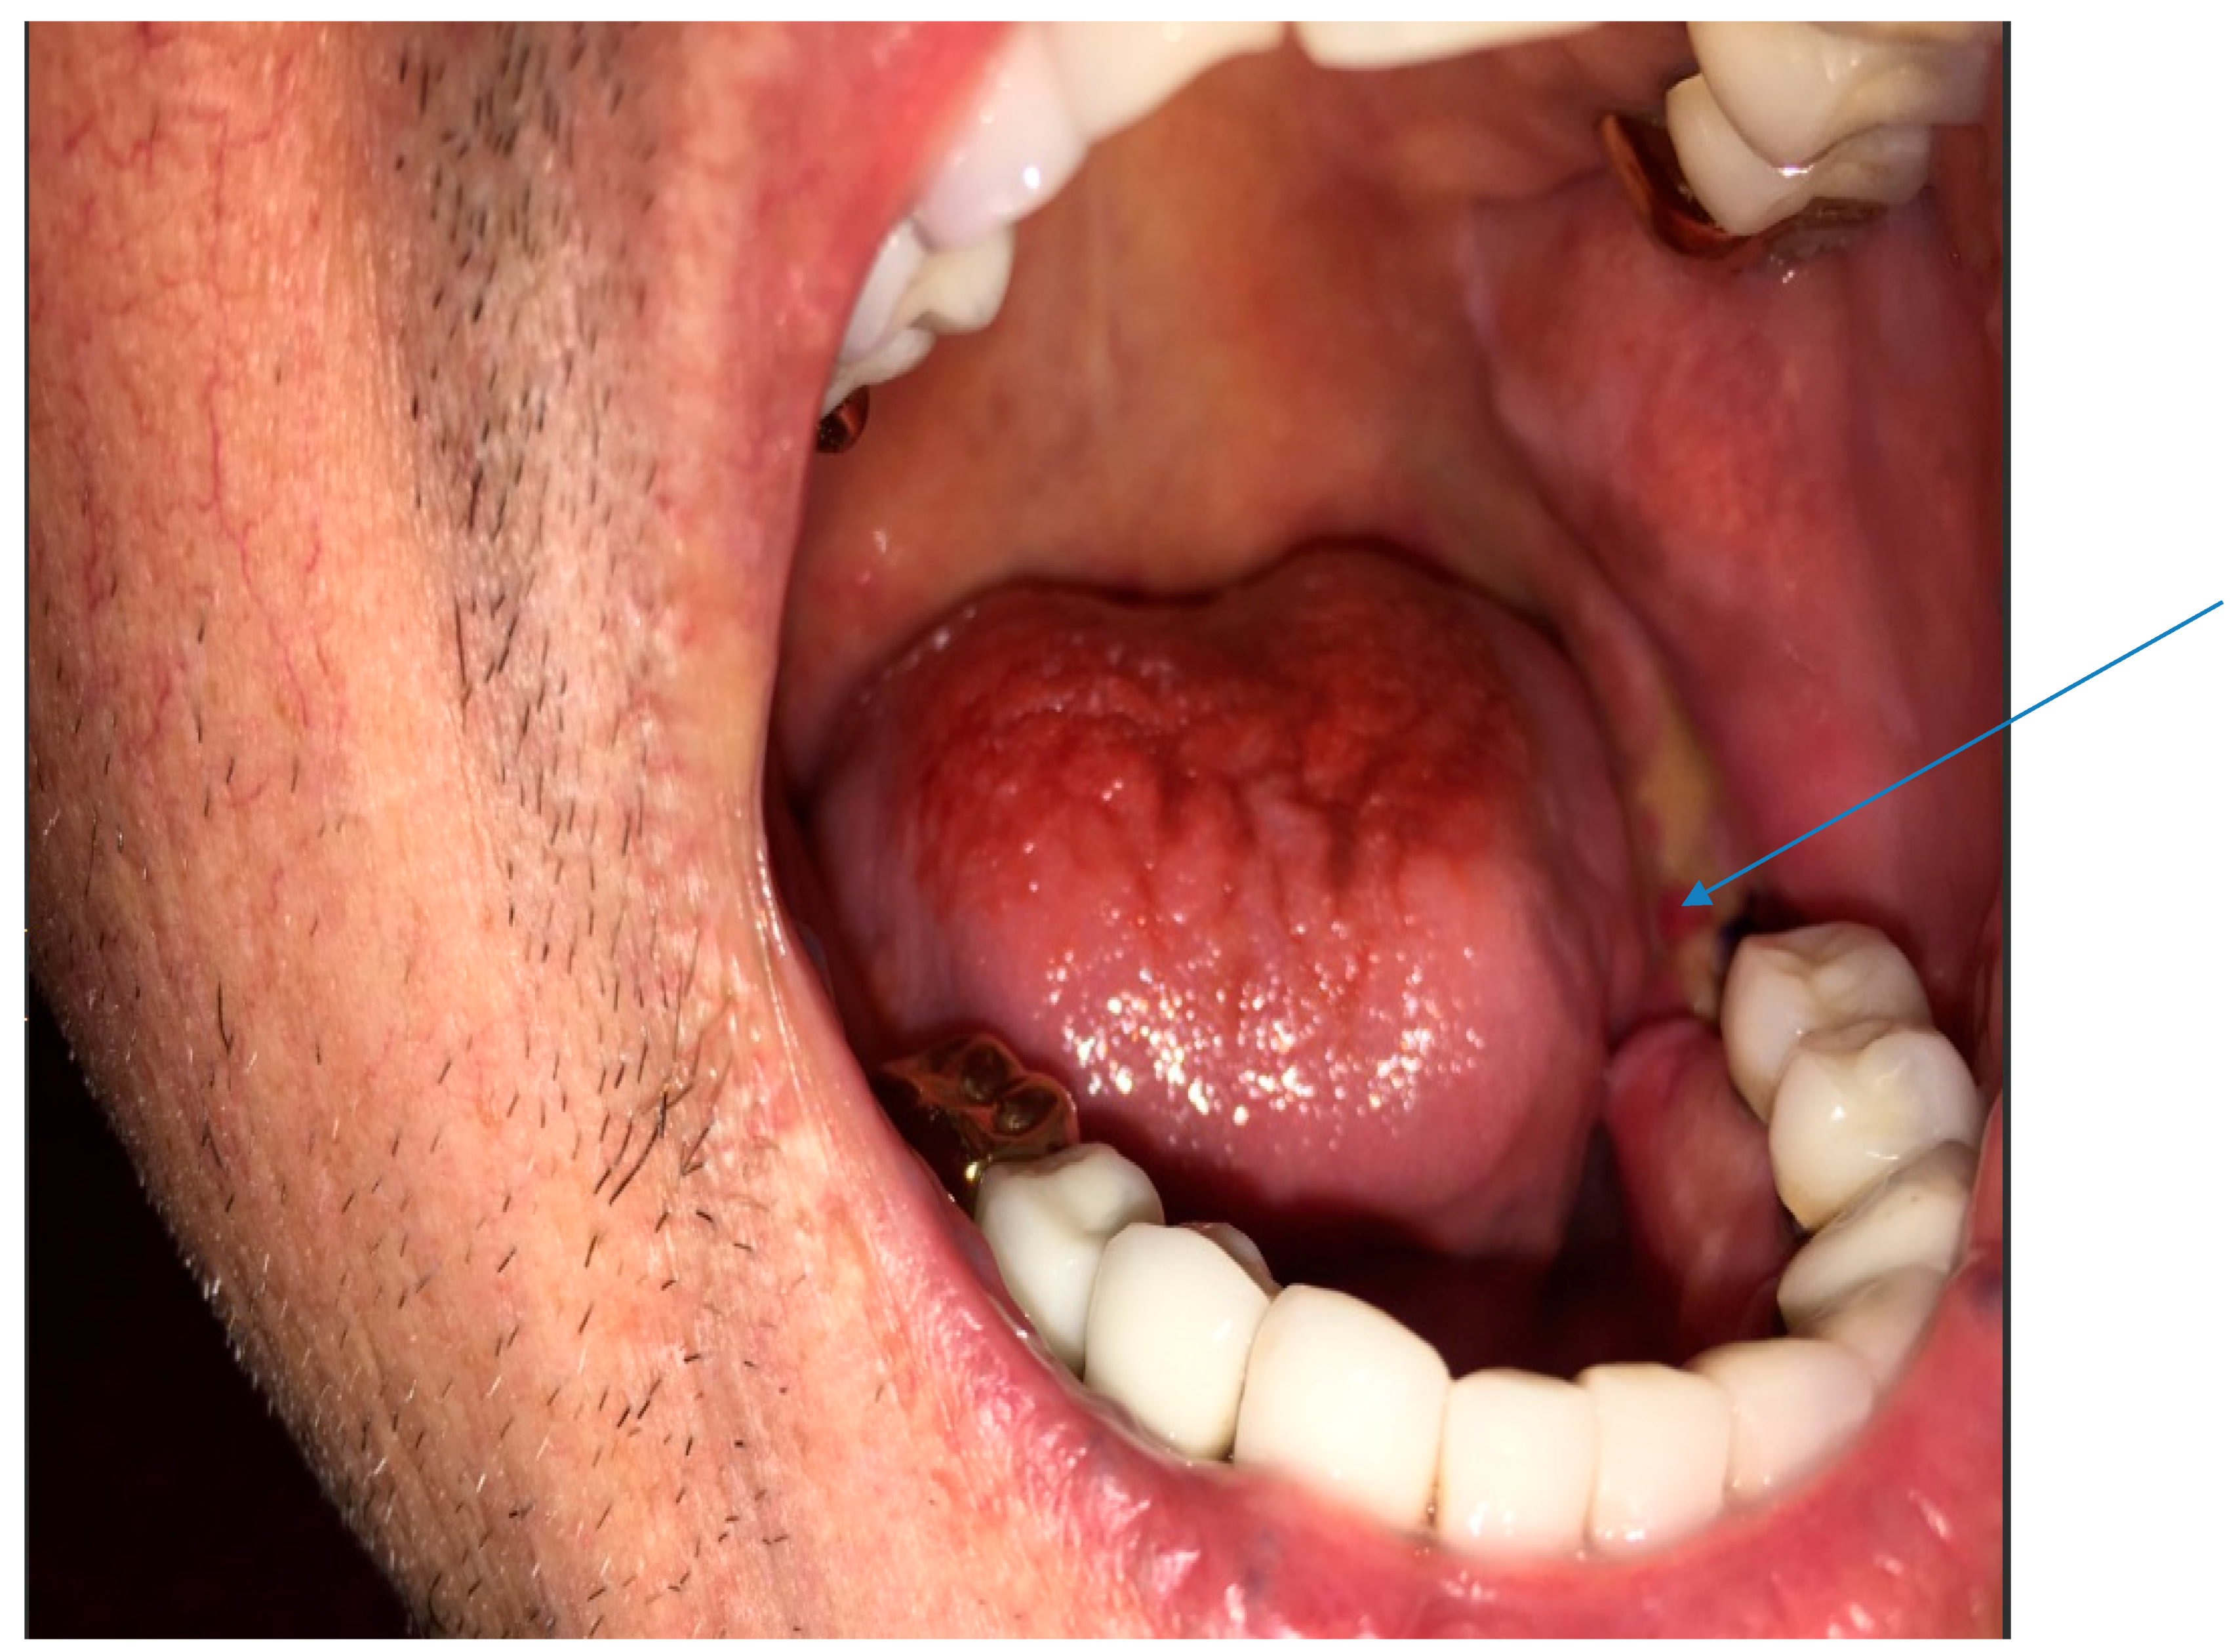

His vital signs were normal. Mouth examination showed exposed bone around the root sites of teeth #18 and 19 (see arrow), with artificial crowns over several teeth in the lower jaw (Figure 1). There were no enlarged cervical lymph nodes and examination of other systems was unremarkable.

Figure 1.

Photograph of the open mouth with arrow pointed at exposed bone around teeth #18 and 19.